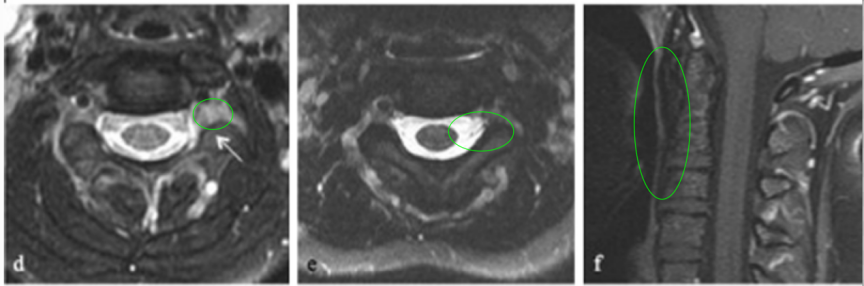

(图6a、b)轴位MRI造影剂及冠状面T2-WI显示一个环形增强的右侧丘脑结节肿瘤。

(图6)

肿瘤累及内侧颞结构(图6c),Rutka教授考虑根据其病情进展制定综合治疗方案,先行经颞中回经脑室入路次全切除肿瘤,组织学为WHO I级毛细胞星形细胞瘤,BRAF重复融合状态为阴性。免疫组化检测BRAF V600E、H3K27M阴性。基因测试证实了NF1基因的变异。术后严密随访患儿术后情况。

(图7)六个月后的影像显示丘脑部分切除和中脑的小肿瘤残留,因此,Rutka教授根据其病情发展量身定制辅助治疗计划,患儿对放疗反应良好。

(图7)